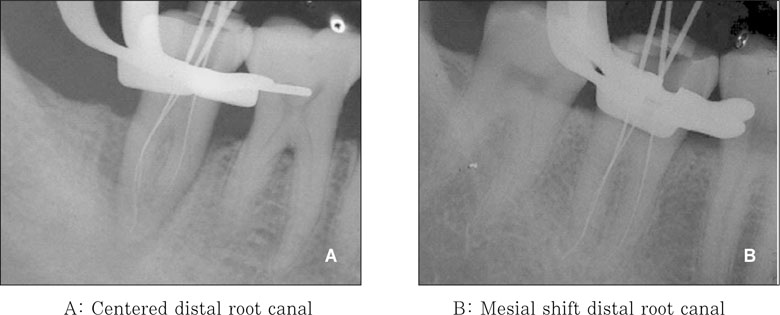

Figure 3

Classification of the location of the distal root canal in a C-shaped root.

jkacd-32-335-g003.jpg

Location of the distal root canal with a C-shaped mandibular second molar.

*: Significantly different at p < 0.01 (χ2 test)

jkacd-32-335-g007.jpg